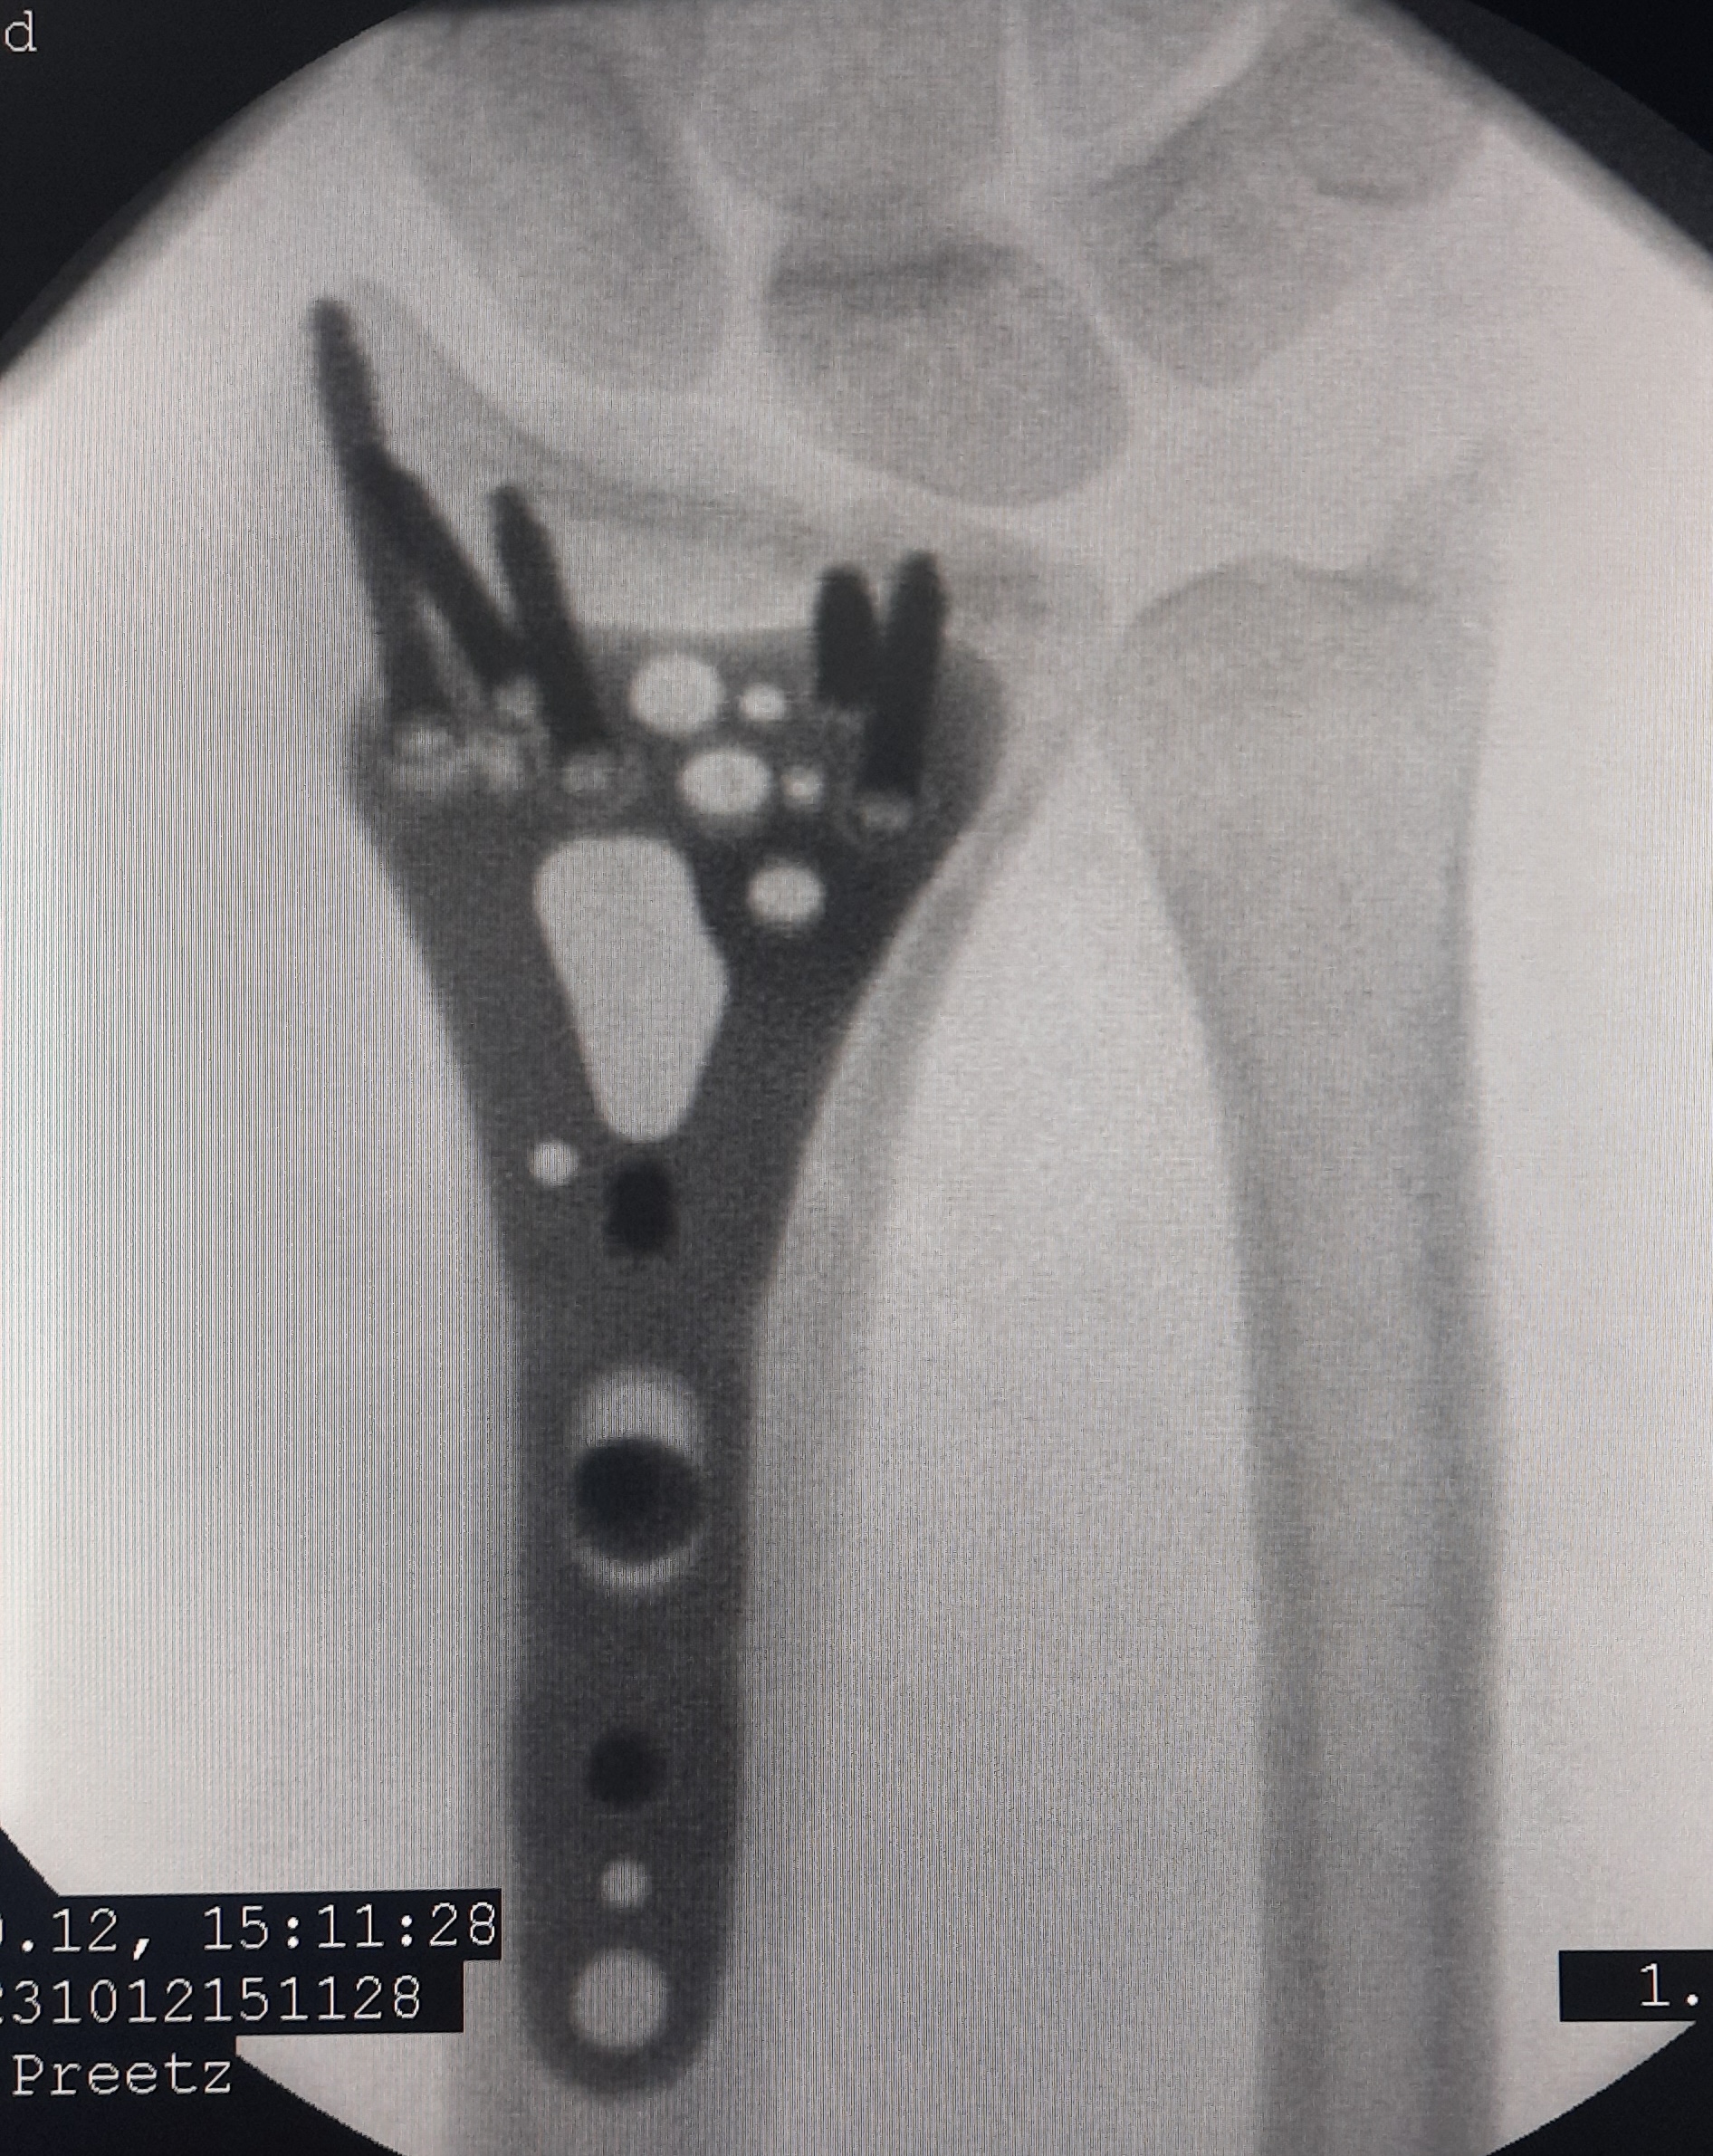

Клинический случай: внутрисуставной перелом дистального метаэпифиза лучевой кости — операция (остеосинтез пластиной)

Этап остеосинтеза: доступ, фиксация и контроль положения пластины.